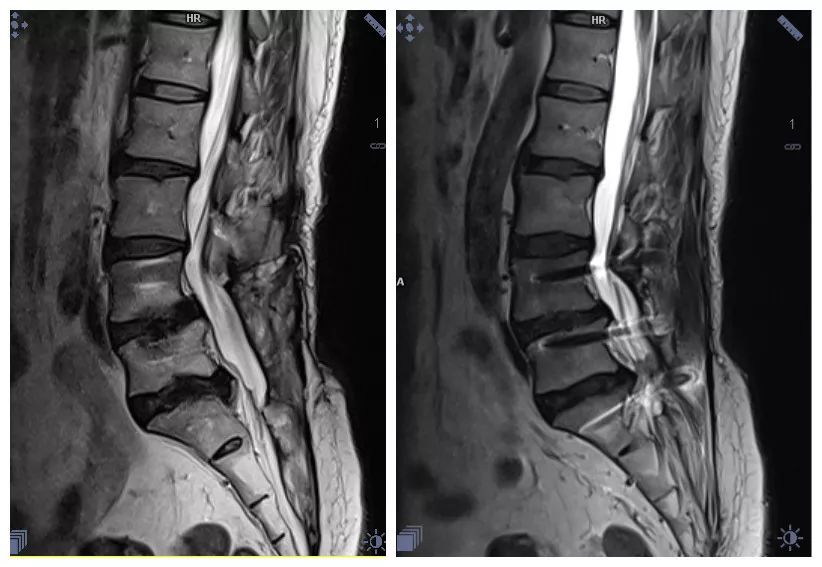

脊髓神经根成像

去金属伪影技术